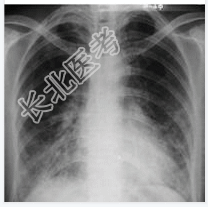

- [材料题] 患者,男性,55岁。咳嗽、发热1周入院。查体:体温,38.1℃;双肺呼吸音粗,双下肺可闻及细湿啰音。心脏听诊无异常。行胸部正位片检查。

- 简答题1、请问该患者诊断是什么?

- 简答题2、请问鉴别诊断有哪些?

- 简答题3、支气管肺炎治疗方法有哪些?